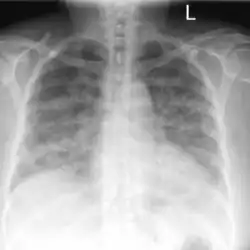

Lung auscultation may reveal abnormal breath sounds such as rhonchi (snoring-like) or crackles (rattling), and chest imaging can show lung consolidations[4] and edema.[5] Decreased lung volumes, including a reduction of average 0.7 liters in forced expiratory volume in 1 second and vital capacity, is found on spirometry. Laboratory studies do not show specific abnormalities, but low oxygen levels in blood, slightly elevated white blood cell count and lactate dehydrogenase levels may be seen.[1]